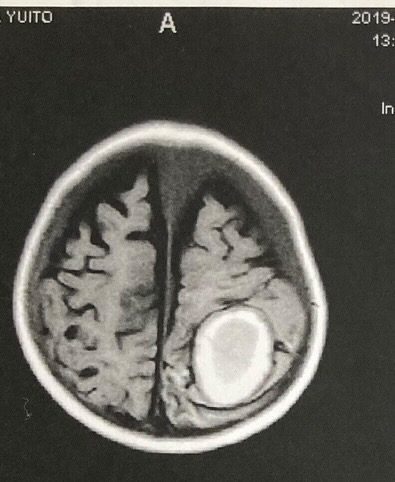

白い部分が脳出血の痕跡。

萎縮して小さくなった脳、本来脳は頭蓋骨内にびっしり詰まっている。(@ahus.tamaさんより提供)